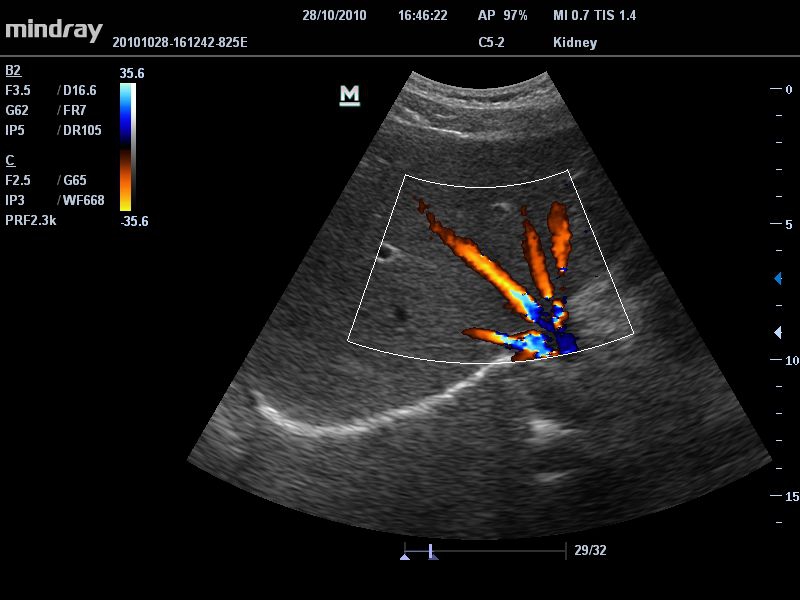

УЗИ-аппарат

Mindray DC-T6

Ультразвуковая система Mindray DC-T6 – это инновационный аппарат для проведения высокого уровня диагностики с качественной визуализацией и широким спектром применения. Платформа рекомендована для использования в коммерчески многопрофильных медицинских учреждениях и государственных лечебных клиниках.

Система поставляется с 15-дюймовым TFT-монитором, а дополнительная эргономика достигается благодаря встроенному кронштейну с угловым механизмом поворота экрана. Это позволяет врачу адаптировать аппарат под свои персональные задачи и обеспечить дополнительный комфорт для пациентов. Благодаря небольшому весу, устройство легко передвигать по территории клиники, в лифтах и ограниченных пространствах.>

Техническая комплектация ультразвуковой системы Mindray DC-T6 включает:

• Монитор: ЖК-дисплей высокого разрешения (15/17 дюймов, на выбор пользователя).

• Специальный кронштейн: Всенаправленный кронштейн с поворотной и регулируемой по высоте панелью управления, обеспечивающий дополнительную эргономику.

• B-Steer™ / iNeedle™: Функция маневрирования ультразвукового луча, улучшающая видимость иглы, нервных волокон и мелких сосудов.

• iStation™: Система управления информацией о пациенте, позволяющая интегрировать, просматривать, архивировать и извлекать данные о пациенте.

• Технология PSH™: Гармоническая визуализация с фазовым сдвигом для улучшения контрастного разрешения и получения четкого изображения с меньшим уровнем шума.

• Формирование мульти-луча: Увеличение скорости обработки сигнала до 8 раз для одного передаваемого луча, обеспечивающее высокое разрешение по времени и частоте кадров.

• Технология iBeam™: Использование нескольких углов сканирования для формирования единого изображения, повышающего контрастное разрешение и качество визуализации.

• iZoom™: Быстрое переключение в полноэкранный режим одним нажатием кнопки.

• iTouch™: Автоматическая оптимизация изображения в режимах B-режима, цветного допплера и импульсно-волнового допплера (PW) одним нажатием кнопки.

• iStorage™: Передача изображений и отчетов на ПК по сетевому кабелю.

• Возможности сетевого взаимодействия: DICOM 3.0, резервное копирование, экспорт, перемещение данных, перезаписываемый DVD, USB-флеш-память.

• Технология iClear™: Автоматическое распознавание структур, обеспечивающее четкие края и контуры, однородное отображение тканей и снижение зернистости в "областях без эхосигнала